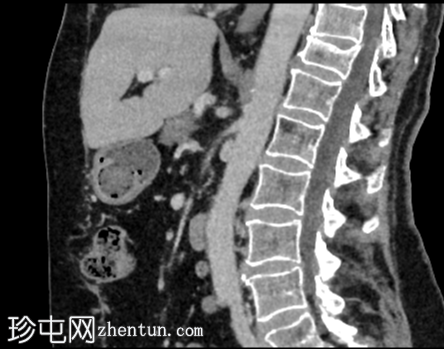

矢状位增强扫描(门静脉期)

4.png

右肾后上极可见2.8 cm外生性强化病灶,提示肾细胞癌(RCC)。右肾静脉和下腔静脉通畅。未见明显局部淋巴结肿大。右肝叶可见高密度金属影。可见含脂肪的脐疝。